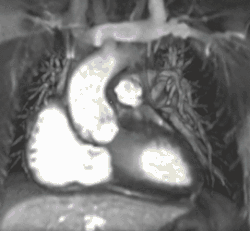

Late gadolinium enhancement

Gadolinium-based contrast agents are administered intravenously and delayed imaging is performed at least 10 minutes later to achieve optimum contrast between normal and infarcted myocardium. An inversion recovery (IR) sequence is used to null the signal from normal myocardium. Myocardial viability can be assessed by the degree of transmural enhancement. Cardiomyopathic, inflammatory and infiltrative diseases may also have distinctive patterns of non-ischemic LGE.[22][23]